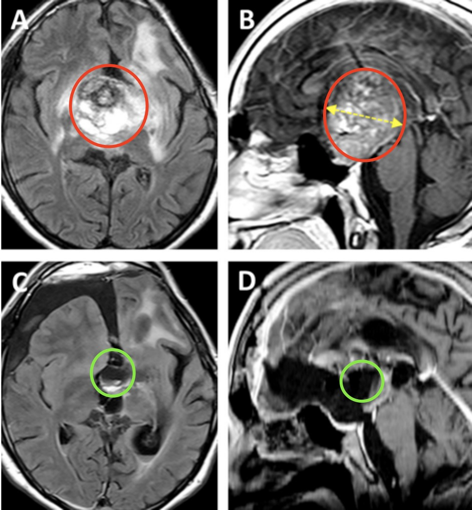

术前情况:术前MRI显示鞍区、丘脑较大肿瘤,侵犯累及左侧海马旁回和侧脑室的上部(图5A、B)。肿瘤体积达68.1mm³,其深度为44.4mm,侧面角为21.9°。

图A、B为术前MRI影像,归类为Bcentral病变的复发性毛细胞星形细胞瘤。黄色虚线表示肿瘤深度(44.4毫米)

手术过程:首先,将累及视交叉的肿瘤切除,在垂体下方发现了垂体柄。前交通动脉和椎板末端逐渐暴露。打开椎板末端可以通畅进入到前三脑室并进行充分瘤内减压。暴露后脑基底分叉和P1节段动脉,尽管肿瘤已被细致切除,下丘脑和后循环血管完整保留。但前交通动脉意外地被拉伸撕裂,由于无法修复撕裂的前交通动脉,因此决定分离前交通动脉,从而在前交通动脉的两个A2段中维持供血,夹闭并分离前交通动脉(图6A-F)。控制好出血及确定血管通畅,可确定残留肿瘤的顺利切除。术后MR提示肿瘤近全切除,两个大脑前动脉A2断动脉血管区域灌注正常(图5C、D),视交叉和视神经束、垂体柄和下丘脑保持原样。

图A、B为术前MRI影像。图C、D显示为几乎全切的术后MRI